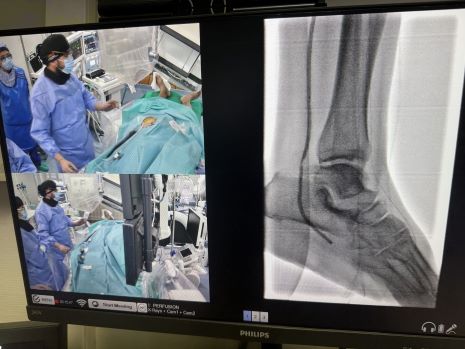

La excelencia del proyecto ha situado al hospital entre los diez centros europeos de aceleración en formación para especialistas en angiología y cirugía vascular y radiología intervencionista. Desde su creación, la Academia organiza de forma periódica cursos y talleres con especialistas de toda Europa, en los que se realizan procedimientos en vivo para mostrar los últimos avances en angioplastias infrapoplíteas, revascularización distal del pie, técnicas de recanalización compleja y punciones retrógradas.

Gallardo destaca además el valor del modelo docente: "En Marbella hemos conseguido crear un espacio de capacitación internacional donde los especialistas pueden implicarse de manera directa en procedimientos complejos. Esa es la clave: no solo enseñar, sino también involucrar en la toma de decisiones durante los casos, porque es la mejor forma de aprender y crecer como profesionales".

El responsable del Servicio hace hincapié en el papel del equipo multidisciplinar: "El éxito de nuestro programa no se entiende sin un trabajo conjunto, el esfuerzo y trabajo de los compañeros de anestesia, técnicos de radiología y enfermería permite que podamos afrontar casos de enorme complejidad y ofrecer a los pacientes alternativas reales a la amputación".